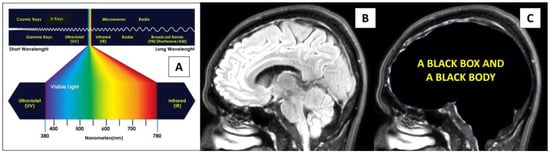

3.1. Physics Perspective on Direct Light Energy onto the Brain